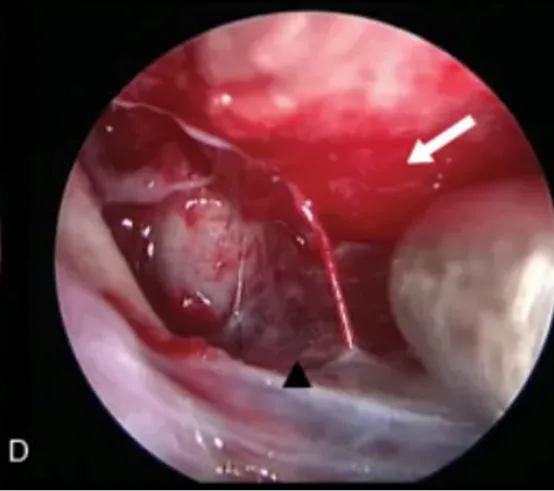

图4(D):使用30度角内镜查看其它潜在潜在的硬膜区域(白色箭头),如果发现,可以电凝处理。

注:ICA,颈内动脉;Left A1,左大脑前动脉;Opht.A,眼动脉;Optic N,视神经。